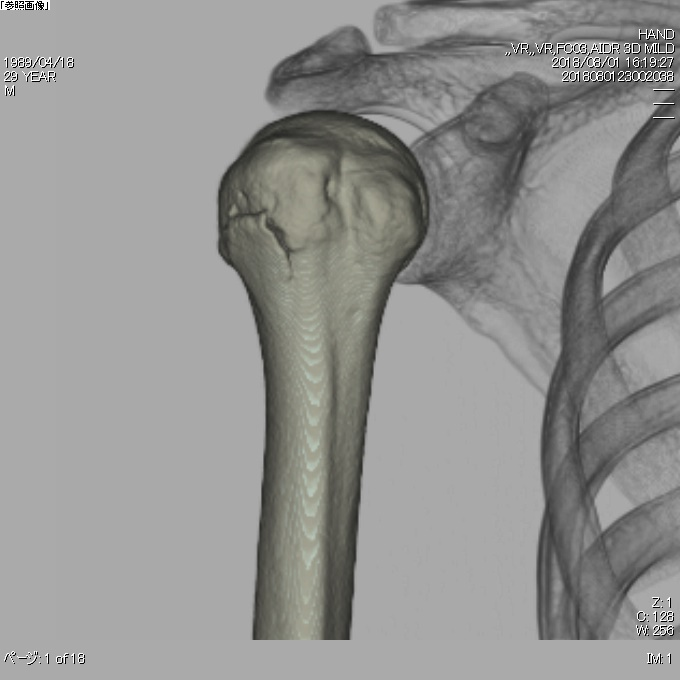

骨密度測定装置

ALPHYS LF

骨粗鬆症は高齢者などに多く見られ、軽度の転倒などで骨折するリスクが高い状態です。

骨折の部位はあらゆる箇所で起こる可能性があり、脊椎圧迫骨折や大腿骨頸部骨折などがあります。

骨塩量は年齢により、減少します。

特に女性の場合閉経期以降に急速に減少します。

当院では整形外科において、治療や治療による経過などを詳しく行っております。

当院の骨密度測定装置は、最新モデルで正確な診断が可能です。

この検査は苦痛もなく、5分程度で終了しますので、安心して検査を受けることができます。